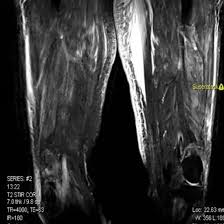

MRI Screening for Left Thigh

Are you looking for reliable MRI screening for the left thigh? Medifyhome works with accredited diagnostic centres to provide high-quality MRI services that accurately diagnose conditions affecting the left thigh, including muscle tears, tumors, and joint issues. Our high-quality MRI screening offers clear images of muscles and tissues, bones, and joints. Medifyhome provides MRI screening for the left thigh in major cities like Chennai, Mumbai, and Hyderabad. Our testing centres prioritize patient comfort and use modern equipment to provide precise results. Each centre is certified by NABL and NABH, ensuring the best quality of care and safety.